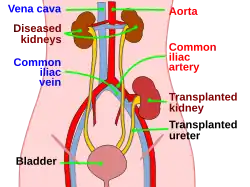

Kidney transplant or renal transplant is the organ transplant of a kidney into a patient with end-stage kidney disease (ESRD). Kidney transplant is typically classified as deceased-donor (formerly known as cadaveric) or living-donor transplantation depending on the source of the donor organ. Living-donor kidney transplants are further characterized as genetically related (living-related) or non-related (living-unrelated) transplants, depending on whether a biological relationship exists between the donor and recipient. The first successful kidney transplant was performed in 1954 by a team including Joseph Murray, the recipient's surgeon, and Hartwell Harrison, surgeon for the donor. Murray was awarded a Nobel Prize in Physiology or Medicine in 1990 for this and other work.[1] In 2018, an estimated 95,479 kidney transplants were performed worldwide, 36% of which came from living donors.[2]

Before receiving a kidney transplant, a person with ESRD must undergo a thorough medical evaluation to make sure that they are healthy enough to undergo transplant surgery. If they are deemed a good candidate, they can be placed on a waiting list to receive a kidney from a deceased donor.[3] Once they are placed on the waiting list, they can receive a new kidney very quickly, or they may have to wait many years; in the United States, the average waiting time is three to five years.[4] During transplant surgery, the new kidney is usually placed in the lower abdomen (belly); the person's two native kidneys are not usually taken out unless there is a medical reason to do so.[3]

Procedure

In most cases, the barely functioning existing kidneys are not removed, as removal has been shown to increase the rates of surgical morbidity. Therefore, the kidney is usually placed in a location different from the original kidney. Often, this is in the iliac fossa, so it is often necessary to use a different blood supply:

- The renal artery of the new kidney, previously branching from the abdominal aorta in the donor, is often connected to the external iliac artery in the recipient.

- The renal vein of the new kidney, previously draining to the inferior vena cava in the donor, is often connected to the external iliac vein in the recipient.

The donor ureter is anastomosed with the recipient bladder. In some cases, a ureteral stent is placed at the time of the anastomosis, with the assumption that it allows for better drainage and healing. However, using a modified Lich-Gregoir technique, Gaetano Ciancio developed a technique that no longer requires ureteral stenting, avoiding many stent-related complications.[63]

Post operation

The transplant surgery takes about three hours.[65] The donor kidney will be placed in the lower abdomen and its blood vessels connected to arteries and veins in the recipient's body. When this is complete, blood will be allowed to flow through the kidney again. The final step is connecting the ureter from the donor kidney to the bladder. In most cases, the kidneys will soon start producing urine.